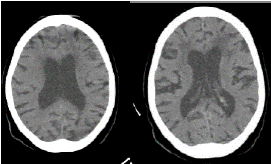

En la tomografía computadorizada (TC) de cerebro, se observó hidrocefalia con ventriculomegalia e hipodensidades periventriculares (figura 1) y en la de tórax de alta resolución, un patrón en vidrio esmerilado con atelectasia del lóbulo inferior pulmonar izquierdo (figura 2).

Figura 1 Tomografía computadorizada de cerebro: se observan hidrocefalia e hipodensidades periventriculares fronto-parietales.